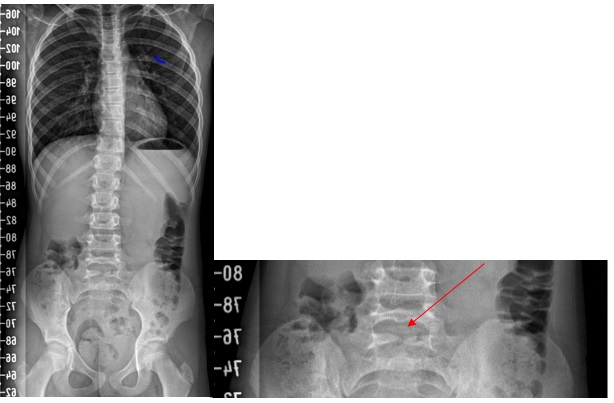

Paciente mujer de 8 años sin antecedentes personales ni familiares de interés. En exploración se detecta dismetría de extremidades inferiores, no visualizada en revisiones previas. Presenta cresta ilíaca y escápula izquierdas más elevadas que el lado contralateral. Se realiza test Adams negativo. Se solicita telemetría mediante radiografía (Fig. 1), en la cual se evidencia leve desviación escoliótica dorsolumbar y raquisquisis de S1. La paciente se encuentra asintomática a nivel neurológico y no presenta alteraciones en la exploración física, habiendo presentado hasta el momento actual adecuado desarrollo psicomotor. Ante el hallazgo casual, se deriva a la paciente a consulta de Neurocirugía y actualmente se encuentra pendiente de valoración.

| Figura 1. A la izquierda, radiografía de columna completa. A la derecha, imagen ampliada donde se visualiza raquisquisis a nivel de S1 |